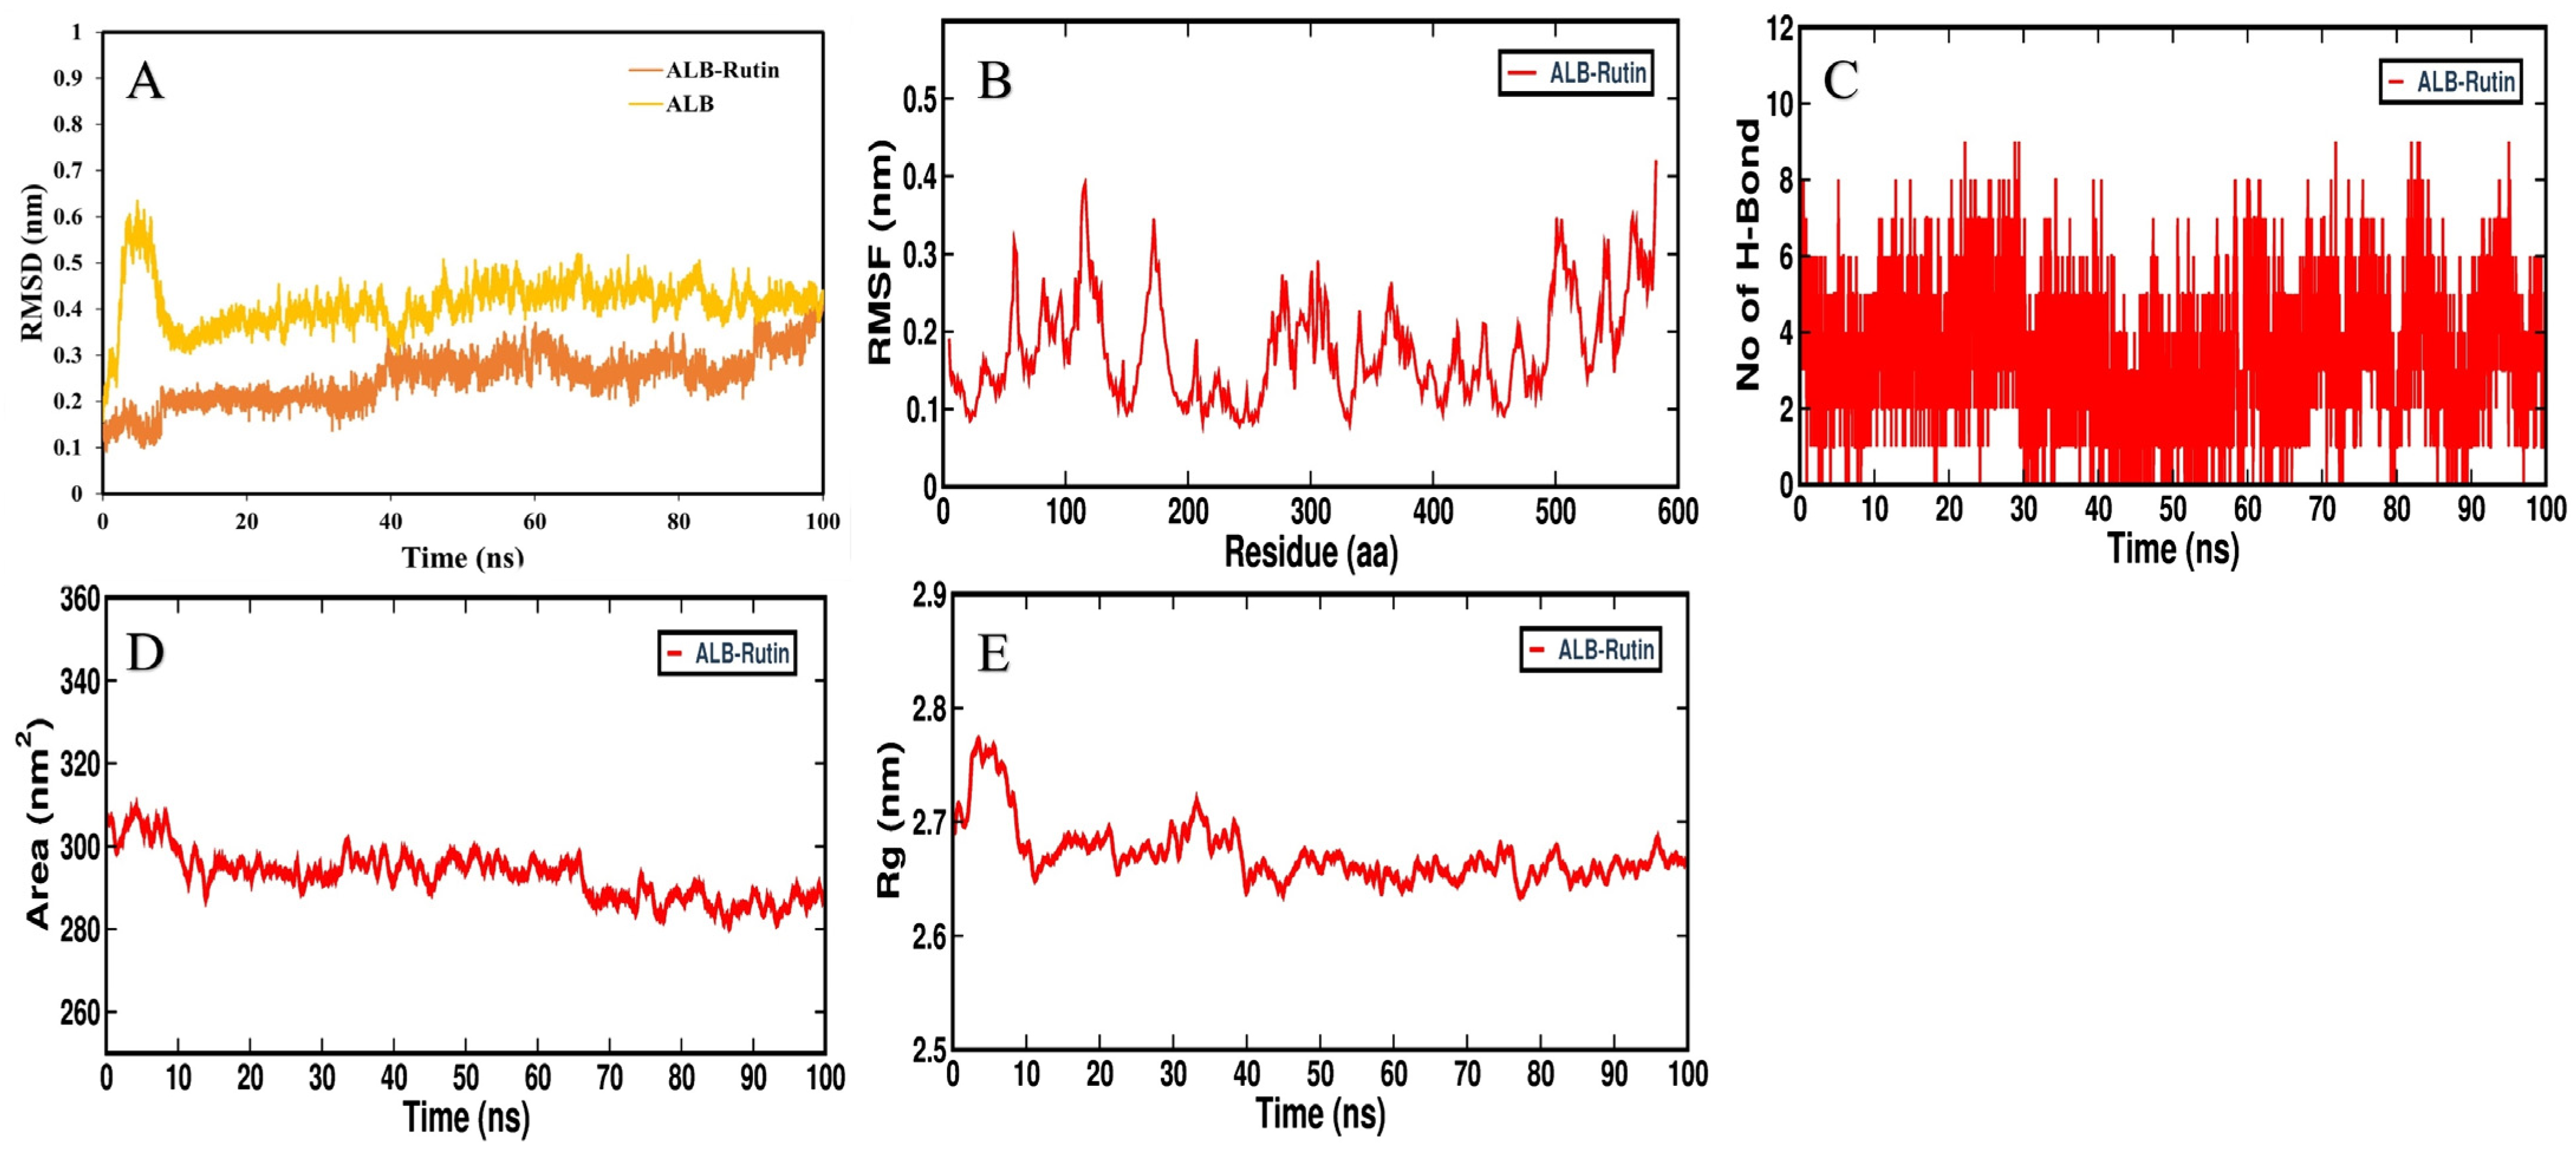

3.5. MD Simulation Analysis

3.6. MMPBSA Binding Free Energy